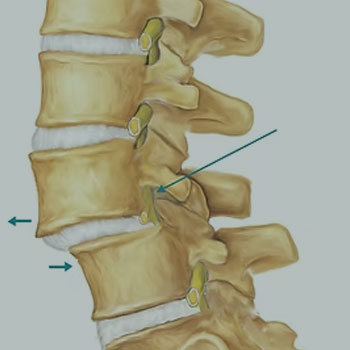

ESTENOSE DO CANAL VERTEBRAL

ESPONDILOLISTESE